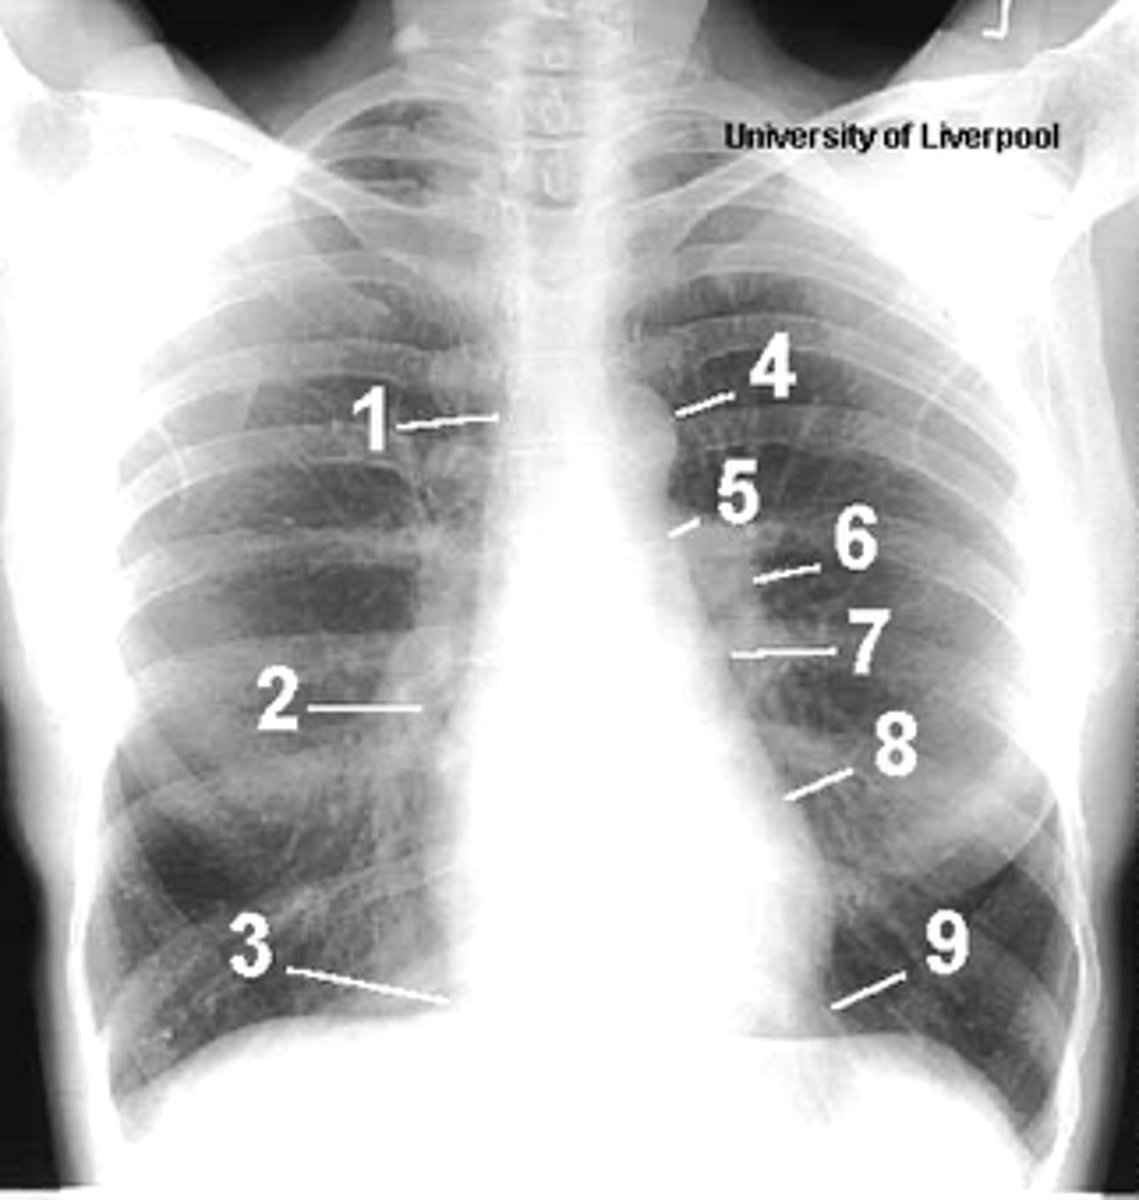

1

superior vena cava

2

right atrium

3

inferior vena cava

4

aortic arch or knob

5

left pulmonary trunk

6

left pulmonary artery

7

left atrium

8

left ventricle

9

left cardiophrenic angle